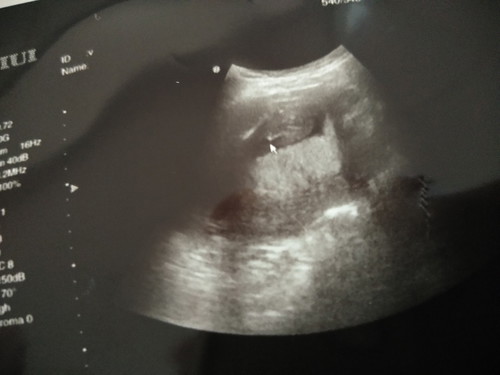

ช่วยดูเพศหน่อยค่ะ

หมอบอกว่าเหมือนเห็นปิกาจู

เราเห็นไม่ชัดเลยคะ

น่าจะชาย